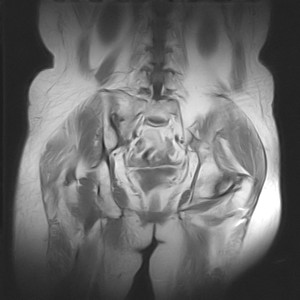

图像太差了 1、右侧臀肌旁脓肿? 建议增强 2、左侧股骨头坏死并半脱位

1、左侧股骨头坏死并髋关节半脱位;

2、右侧臀肌感染,(可能褥疮所致)